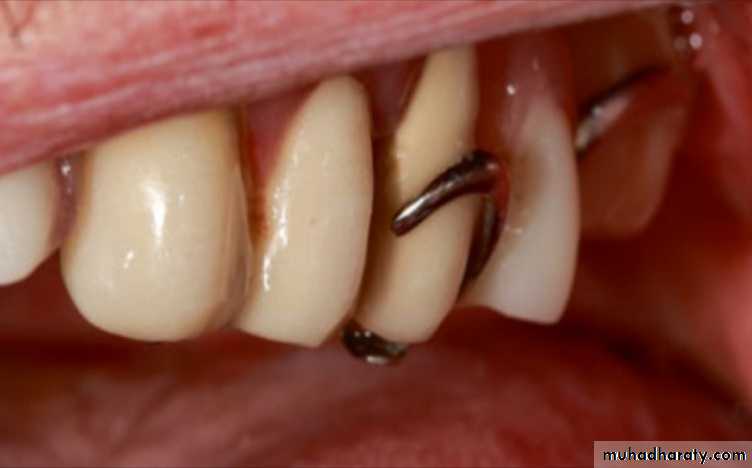

Distortion of the RPD may occur if the patient tries to tighten the RPD or uses the

clasps while insertion and removal.

The distorted clasps may be changed with wrought wires or cast clasps by the laboratory after making an impression with the RPD.